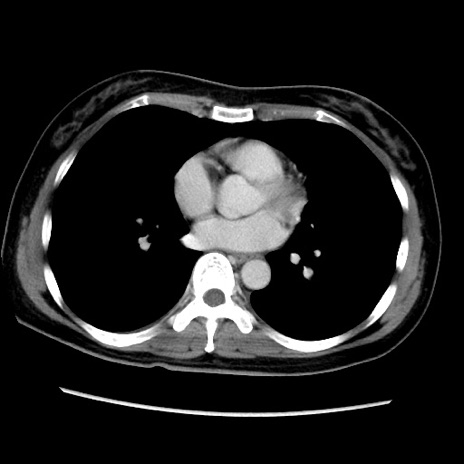

症例39(横断像)

【症例】40歳代女性

【主訴】上下腹部痛

【現病歴】2日目から下腹部痛あり。夜間は痛みで眠れなかった。昨日より上腹部痛と下痢が出現。臥位で痛みは軽快したため、休んでいた。本日になって臥位でも立位でも痛みが強くなってきたため救急要請。

【既往歴】子宮内膜症

【身体所見】部:平坦・軟、左上下腹部に圧痛あり、反跳痛あり。

【データ】WBC 21800、CRP 26.78